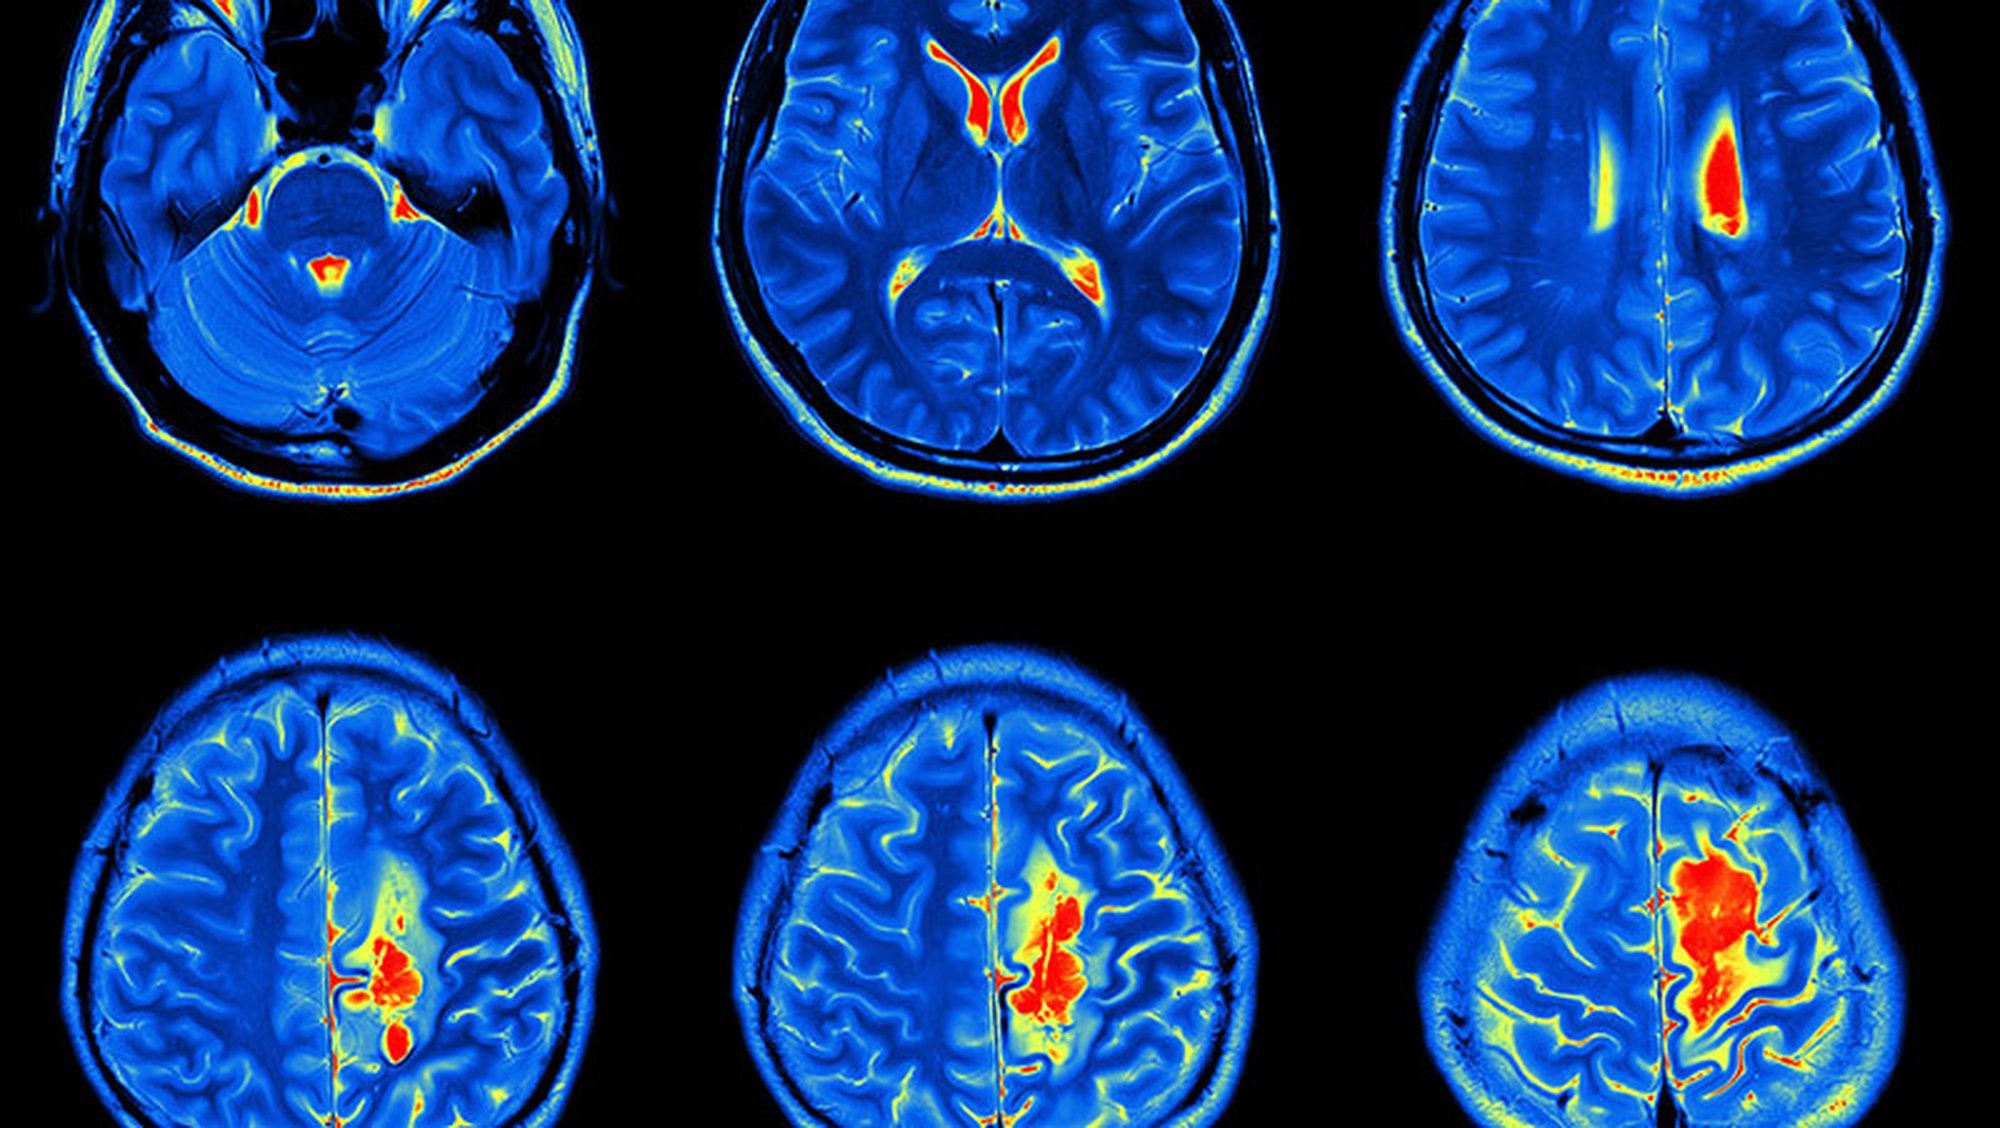

Beyindeki hücrelerini yenilenirken meydana gelen hatalı anormal hücrelerin büyümesi, kolonileşmesi sırasında meydana gelen yapıya “beyin tümörü" denir. Beyin tümörleri doğrudan beyin hücrelerinde ya da vücudun başka organlarından sirayet etmiş kanserli hücreler olabilir. Beyin hücrelerinde meydana gelen tümörlere “primer” beyin tümörü organlardan sirayet etmiş hücrelere “seconder ” ya da metastaz denir. Beyin tümörleri iyi huylu(benign), kötü huylu(malign) olarak ikiye ayrılır.[1], [2], [3], [4]

Beynin kendi hücrelerinde meydana gelen bozuklukların büyük kısmı kötü huylu tümörlerdir, DNA yenileme sürecinde meydana gelen bir hata nedeniyle oluşan hastalıklı hücrelerin toplanmasıyla oluşur tedavisi çoğunlukla ameliyattır, ameliyatla kötü huylu tümörlerin tamamen alınması tümörle beyin dokusu arasında iyi huylu tümörlerdeki gibi bir kapsül veya benzeri bir yapı olmadığından ameliyatla alınan tümörlerin tamamen alınması mümkün değildir bu yüzden ameliyattan sonra tümörün tekrar büyümesi olasıdır, kötü huylu tümörlerin 4 seviyesi vardır 1. ve 2. seviyedeki tümörler düşük seviyeli tümörlerdir ve seyri ve tedavisi 3. Ve 4. Seviyedeki tümörlere göre nispeten daha iyidir 3.(Anaplastik) ve 4. (Glibostroma multiforme) seviyeli tümörler daha yüksek seviyelidir.

Beyin tümörünün görülme oranı %3-%5 arasındadır, erkeklerde görülme oranı kadınlarda görülme oranına göre daha çoktur. Beyin tümöründe ölüm oranı son yıllarda tıptaki gelişmeler sebebiyle ölüm riski %25-%30 iken %2-%3 e düşmüştür, bunun yanında felç, denge bozuklukları, konuşma bozuklukları gibi nörolojik problemler görülme riski de vardır.[1], [2], [3], [4]